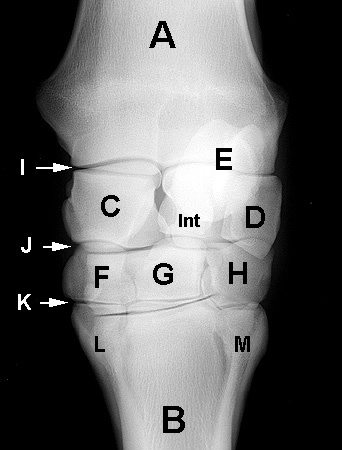

A. Radius

B. Third metacarpal

C. Radial carpal

D. Ulnar carpal

E. Accessory carpal

F. Second carpal

G. Third carpal

H. Fourth carpal

I. Antebrachiocarpal joint

J. Middle carpal joint

K. Carpometacarpal joint

L. Second metacarpal

M. Fourth metacarpal